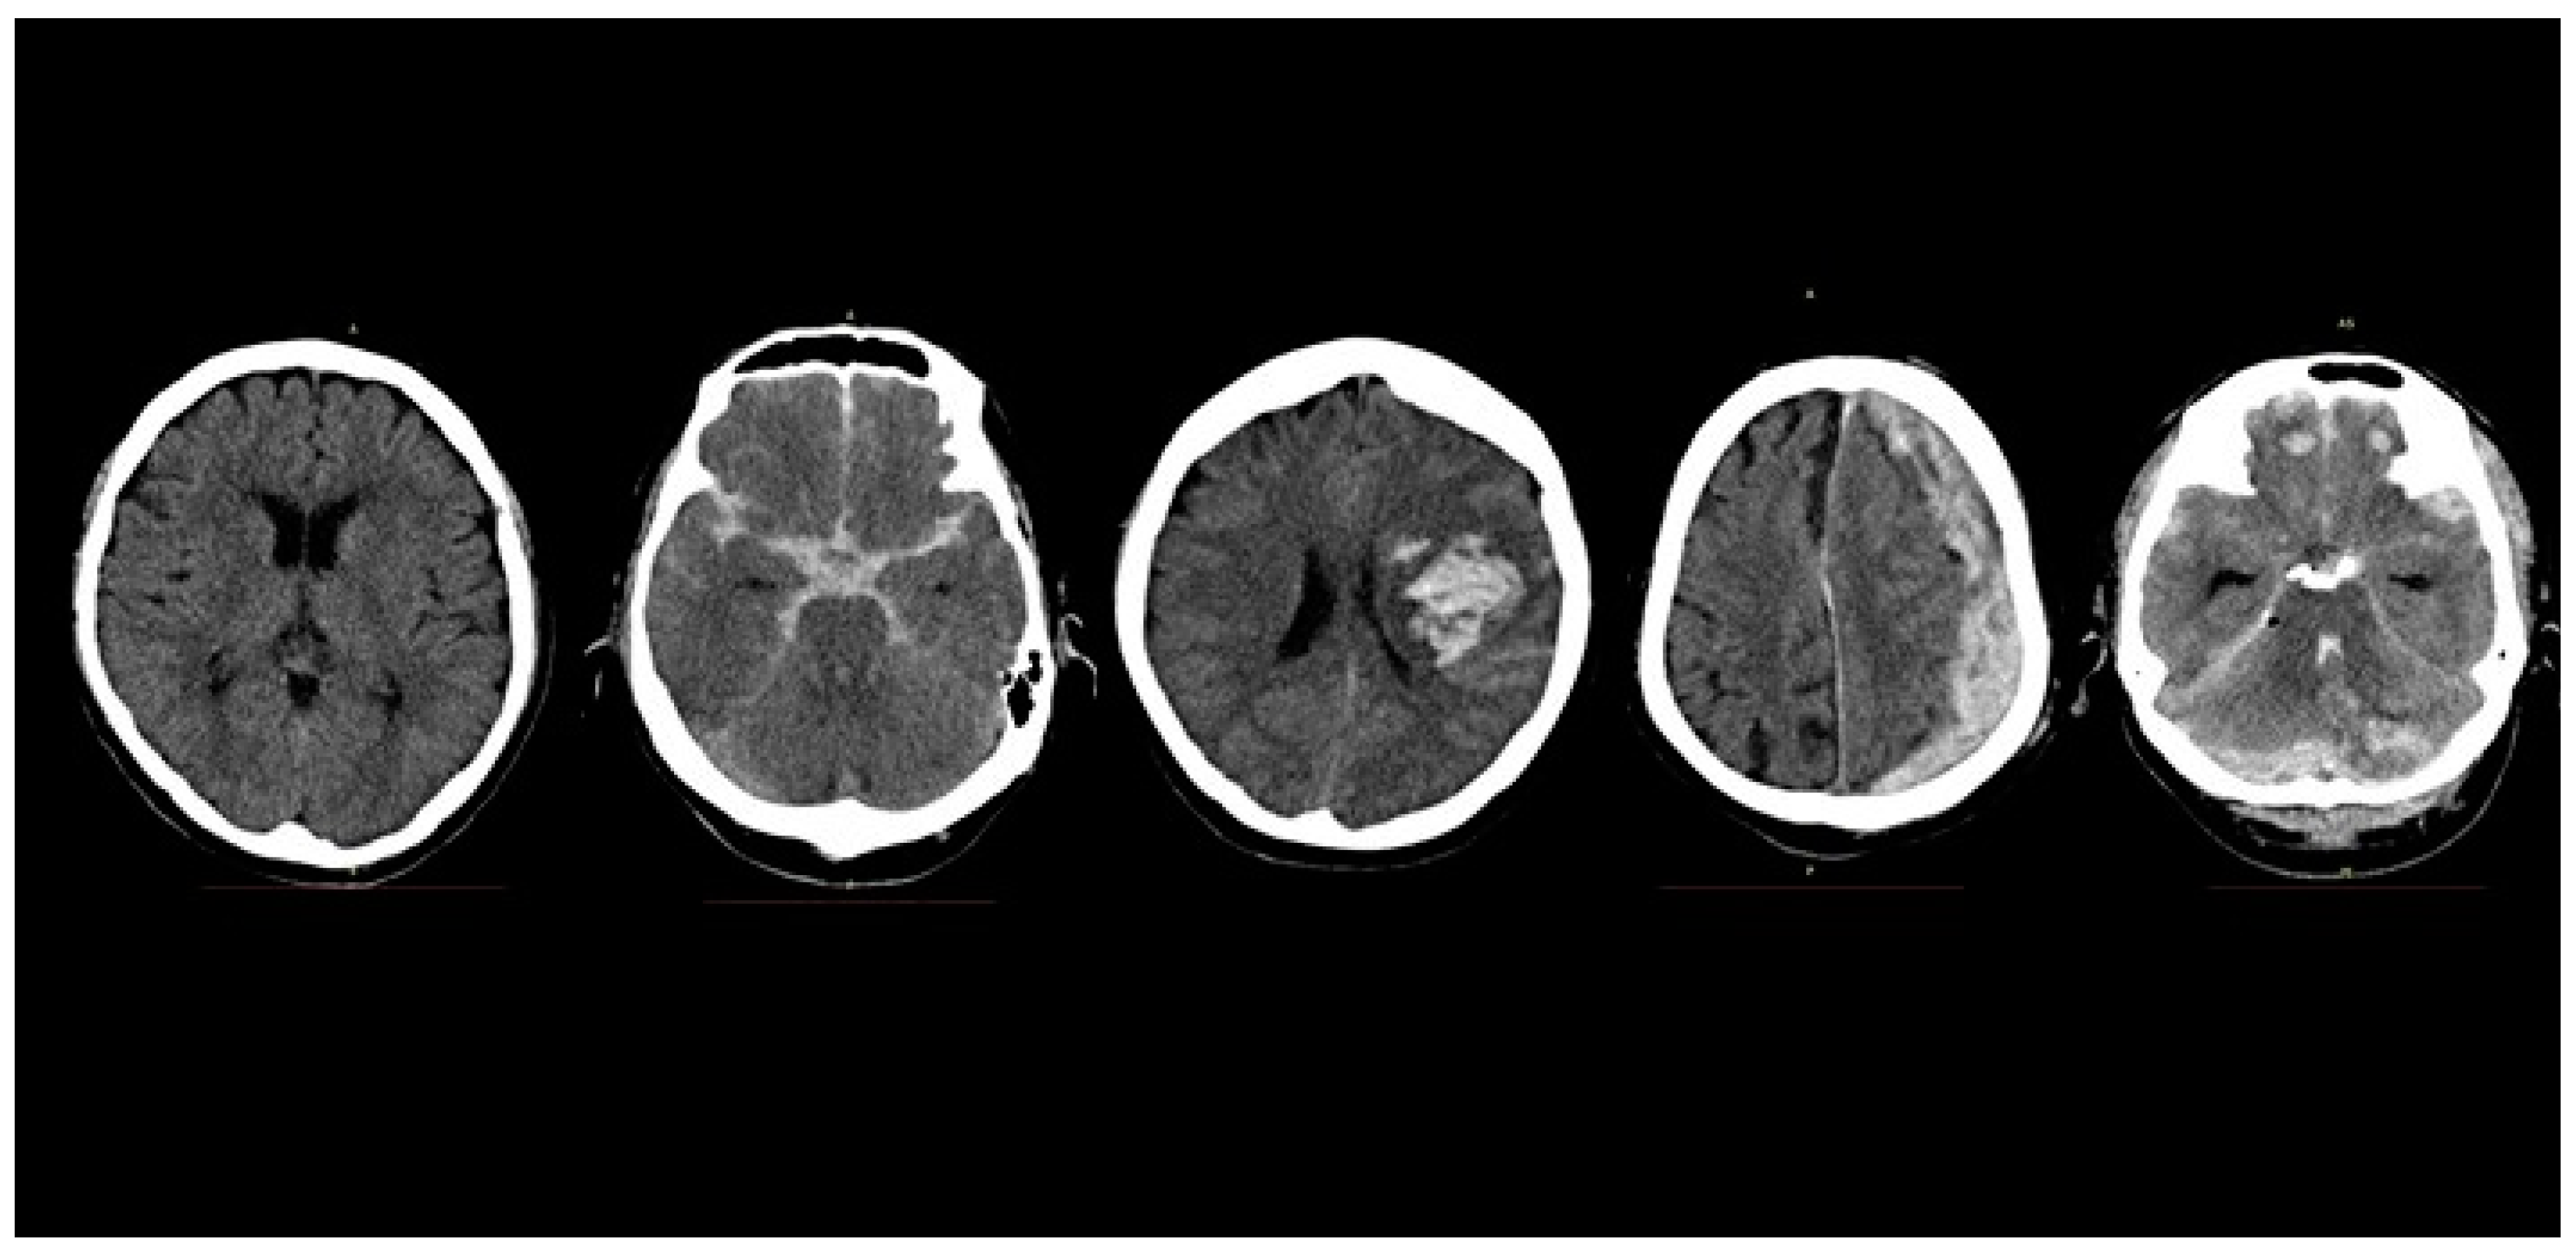

Image Thresholding Improves 3-Dimensional Convolutional Neural Network Diagnosis of Different Acute Brain Hemorrhages on Computed Tomography Scans